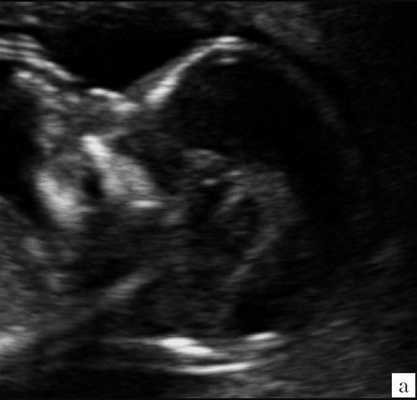

Самый тяжелый и инвалидизирующий порок в области задней черепной ямки - аномалия Денди-Уокера, характеризующаяся наличием кистозного образования в области большой цистерны с аплазией червя мозжечка. Наш опыт показывает, что в I триместре в срок 12 недель при осмотре аксиального среза головы плода можно визуализировать кистозное образование в области задней черепной ямки, однако провести дифференциальный диагноз между различными патологиями этой области, имеющими разный прогноз, по этому скану невозможно (рис. 9).

Рис. 9. Аксиальный срез головы плода, киста задней черепной ямки, беременность 12 недель.